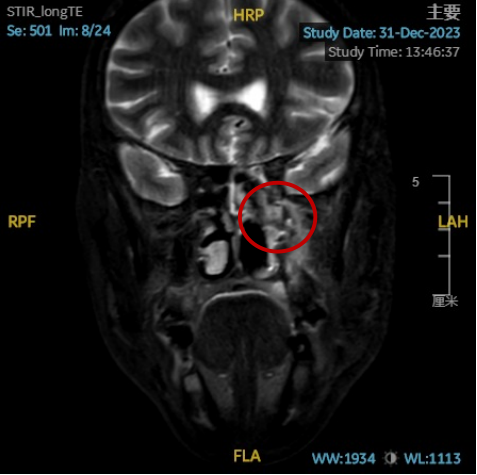

术后